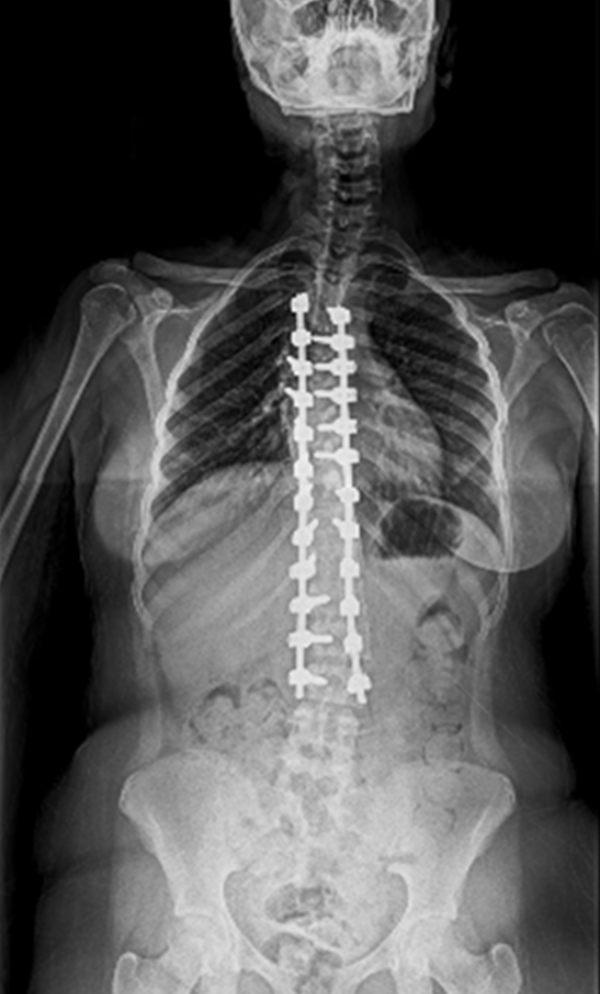

BEYOND RECOVERY : REAL STORIES

Gallery : Before - After